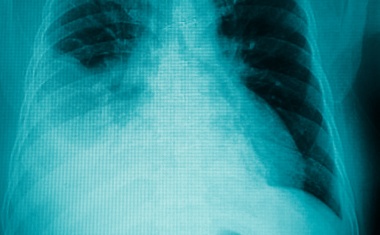

Die Unimedizin Greifswald setzt bei Beatmungspatienten auch künftig auf eine medizintechnische Neuentwicklung aus Kanada.